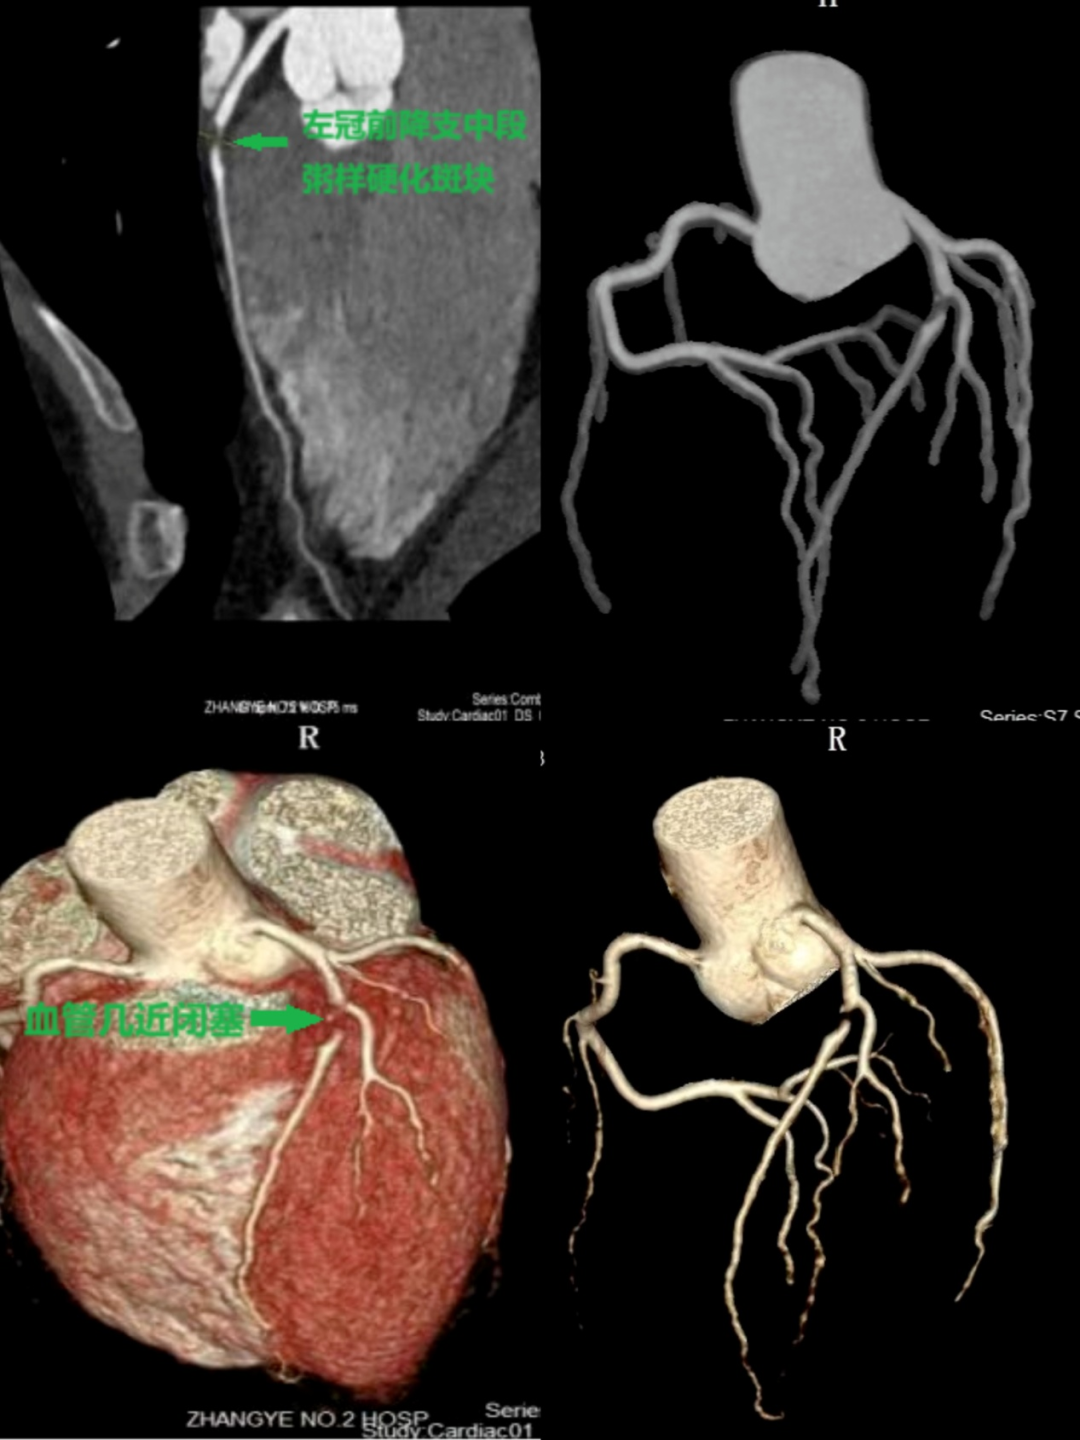

下圖是賈先生2024年10月在我院做的冠狀動脈CTA圖像,顯示左冠狀動脈前降支中段粥樣硬化斑塊形成,管腔重度狹窄,血管幾近閉塞。

家住肅州區(qū)的賈先生,今年45歲,由于工作比較特殊,經(jīng)常加班熬夜。最近,賈先生總感覺胸口悶悶的,像壓著一塊大石頭,于是到我院心腦血管病門診咨詢。經(jīng)過認(rèn)真詢問,了解到賈先生不僅經(jīng)常熬夜,還大量吸煙,盡管賈先生比較年輕,醫(yī)生還是考慮可能是心臟的冠狀動脈出了問題,于是為他安排了冠狀動脈CTA檢查。結(jié)果顯示有一根冠狀動脈形成了斑塊,幾乎堵塞了整個血管,導(dǎo)致心臟局部缺血。幸虧臨床醫(yī)生判斷準(zhǔn)確并及時處理,賈先生住院后在左冠狀動脈前降支放了一枚支架,經(jīng)過系統(tǒng)治療后賈先生很快恢復(fù)健康,重新投入到工作中。